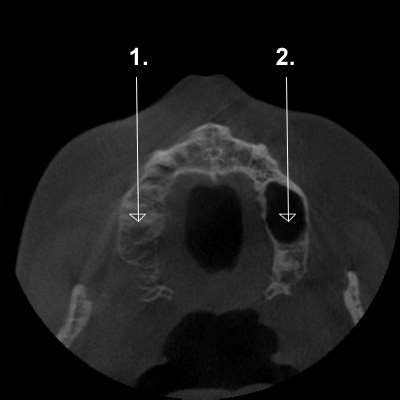

Ik heb hier een afbeelding van een 3D scan van de kaak,

en zou graag willen weten waarom de ene kant zwart is en de andere kant "mistig"…

Zie #1 en #2.

Sinusholte bij 1 laat sluiering zien.

De sinus kan vol vocht zitten,

de mucosa kan zodanig dik zijn dat de volledige sinusholte erdoor gevuld wordt; ook als het slijmvlies van de voorwand van de sinus zeer gezwollen is geeft dit een sluiering van de totale sinus; er kan agenesie van de sinus zijn. Bij totale sluiering is dus verder onderzoek vereist.